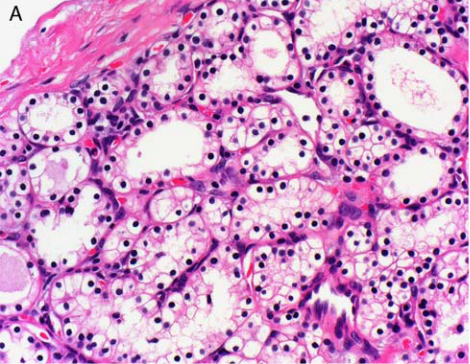

您的位置首页百科知识 浆液腺 Simone 发布于 2025-09-18 21:57:48 914 阅读 浆液腺的有关信息介绍如下:一般指分泌浆液的外分泌腺而言。由1个乃至多个浆液细胞构成,与粘液腺相对而言。广泛分布于动植物体,在高等动物多散在于口腔、鼻腔、气管、食管、胃、肠、排泄器官等处,参与浆液的形成。想要了解更多“浆液腺”的信息,请点击:浆液腺百科